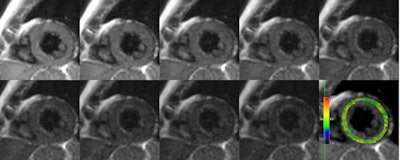

Raw MRI images with corresponding color T2 map in a healthy volunteer, acquired with a Gradient Spin Echo (GraSE) technique using nine gradient-recalled echoes.